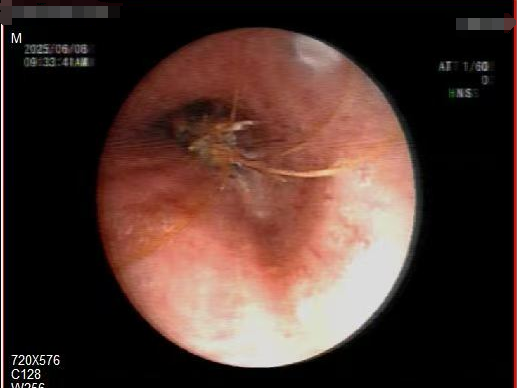

胸部CT显示,河虾已经下滑并卡在左主支气管管口。